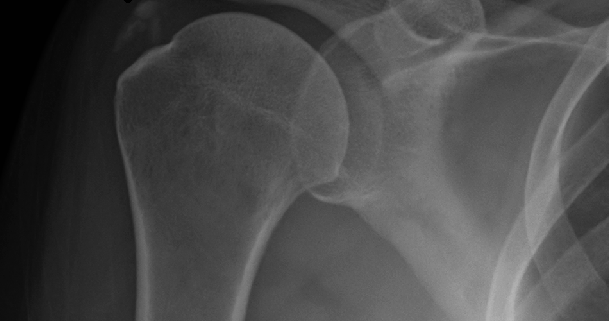

Diagnosing calcific tendonitis typically begins with a physical examination of the patient’s shoulder. Your doctor may palpate the shoulder to identify any areas of tenderness or inflammation. Imaging tests, such as X-rays, MRI scans, or ultrasound, may be performed to confirm the presence of calcium deposits in the tendons.